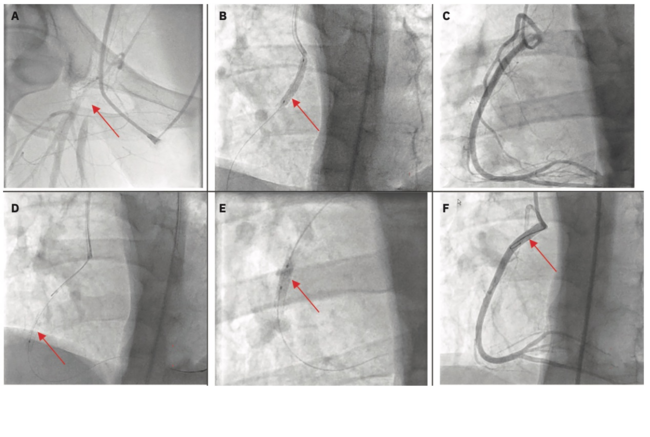

Coronary Stent Migration Induced by Undersized Stent and Arterial Vasospasm

Stent migration in a coronary vessel is a rare phenomenon that can occur during a percutaneous coronary intervention (PCI). It is infrequently reported in the literature and occurs 0.3% to 1.3% of the time during PCI.1 There are many reports of intracoronary stent entrapment, stripping, and dislodgement during PCI; however, reports of migration are limited.2 The most common cause of stent loss is balloon dislodgement during implantation.1 It can also occur during a pullback and vasodilator therapy use during the procedure. Most reported cases of coronary stent migration have occurred in older patients undergoing PCI to increase coronary vascular flow. Here, we share the case of a 23-year-old patient with Noonan syndrome who experienced stent migration during PCI due to vasospasm.